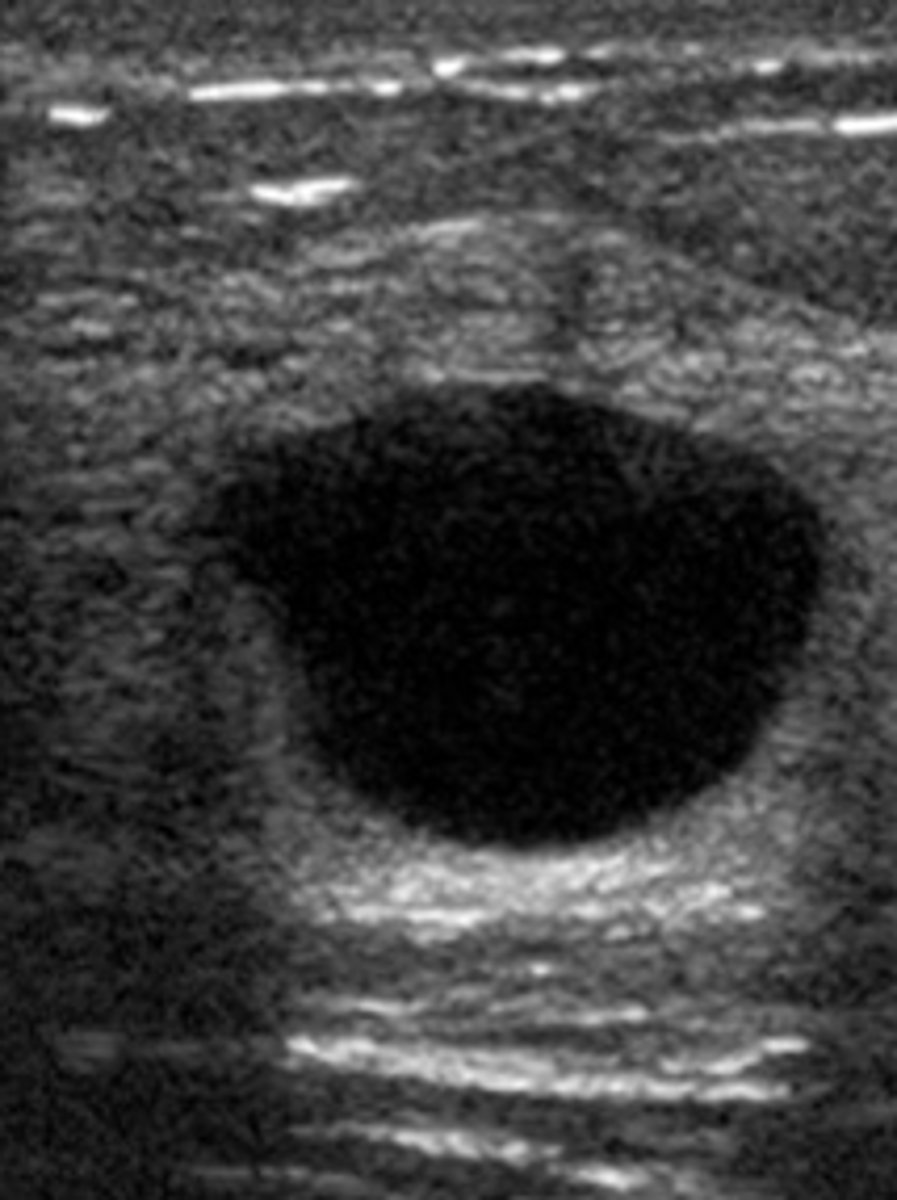

B. rectification

What is another name for the hyperechoic artifact distal to a fluid-filled structure

A. refraction

B. shadowing

C. speckle

D. grating lobe

E. enhancement

enhancement

<p>enhancement</p>